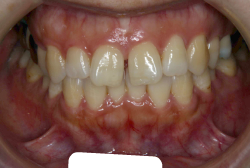

「歯並びの凸凹を直したい」という主訴で来院したケースです。診断の結果、たしかに「叢生」という隙間が足りないと言うことが原因の凸凹症例でした。

しかし、それ以上に問題なのは「前歯の噛み合い方が深すぎる」という症状で、初診の歯の正面写真を見ると下の前歯が全く見えません。こういう症状を矯正学では「過蓋咬合(かがいこうごう)」と言います。過蓋咬合を放置すると、将来的に顎関節に悪影響を与えるとされており、顎関節症の原因因子の一つです。また下の前歯の先端が、上の前歯の裏側の歯茎と強く接触するため、歯周病の原因にもなります。

検査の結果、凸凹が軽症なため非抜歯で矯正すること可能と判断、マルチブラケット装置にて治療しました。治療後は歯並びが綺麗になっただけでなく、噛み合わせ的にも正しい状態が確立しています。